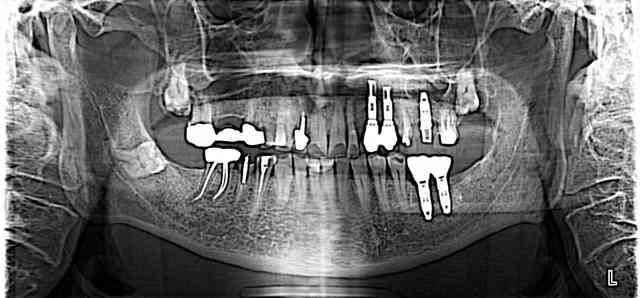

Patient de 68 ans, de retour en France jusque fin Août, désire refaire le haut: il présentait à la première consultation un bridge auro-céramique de 17 à 15 réalisé il y a 20 ans sur dents vivantes par un ponte de la région.

Il a différents travaux implantaires et prothétiques faits dans de nombreux pays (Afrique du Sud...) et est surtout bruxomane (port d'une gouttière qui sera refaite une fois les travaux terminés).

Les implants en lieu et place des 36 et 37 supportent des couronnes en or, et je ne compte pas y toucher.

La 27 va être couronnée en or (on récupère l'or du bridge et comme en face, c'est de l'or, ça ne me semble pas trop mal).

L'implant en 26 va être couronné.

La 15 vient d'être extraite (elle était fracturée sous le bridge et est venue au premier coup d'arrache-couronne) et je m'apprête à faire un bridge de 14 à 17 sur dents vivantes, mon prothésiste, pas mauvais en fixée, me propose un bridge e-max de 14 à 17 en m'en garantissant la solidité.